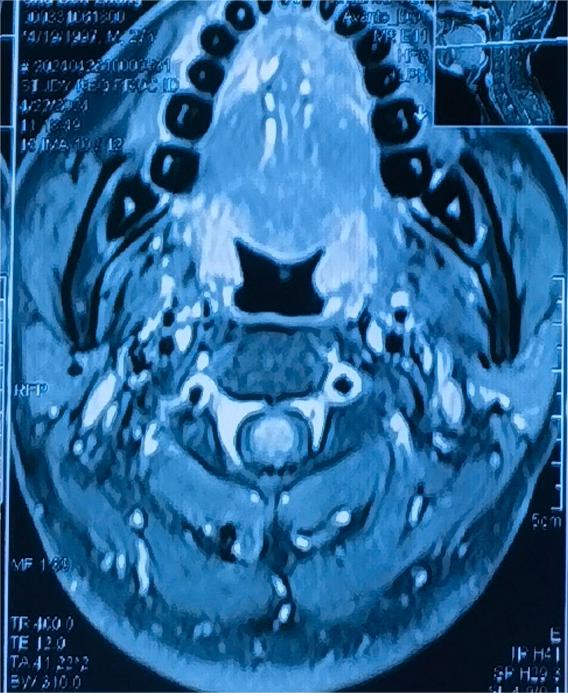

入院查头颈部MR提示C1到C2髓内占位,脊髓肿胀明显